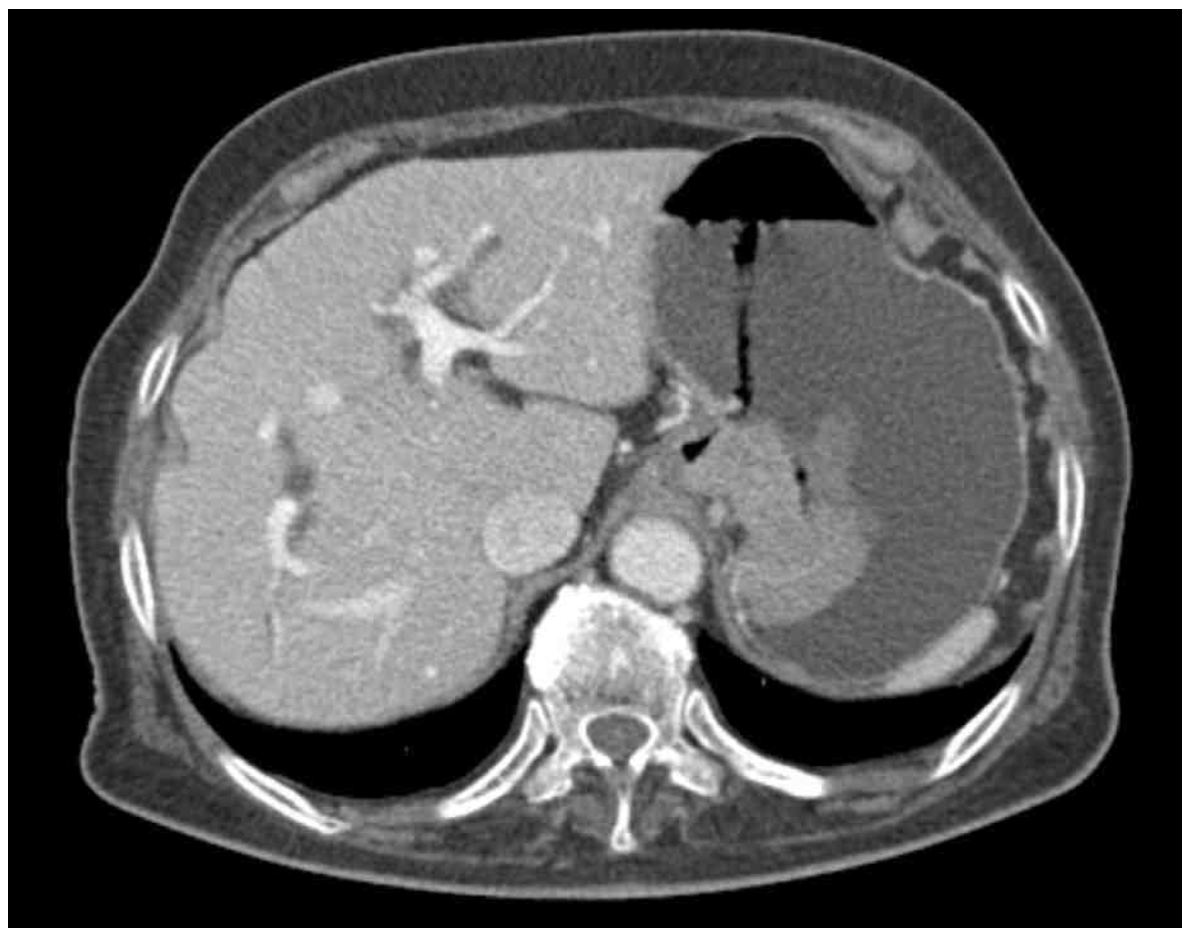

CT: Large gastric mass, protruding towards lumen

• 복부 CT에서 또한 위 내부로 돌출된 gastric mass소견이 관찰된다.